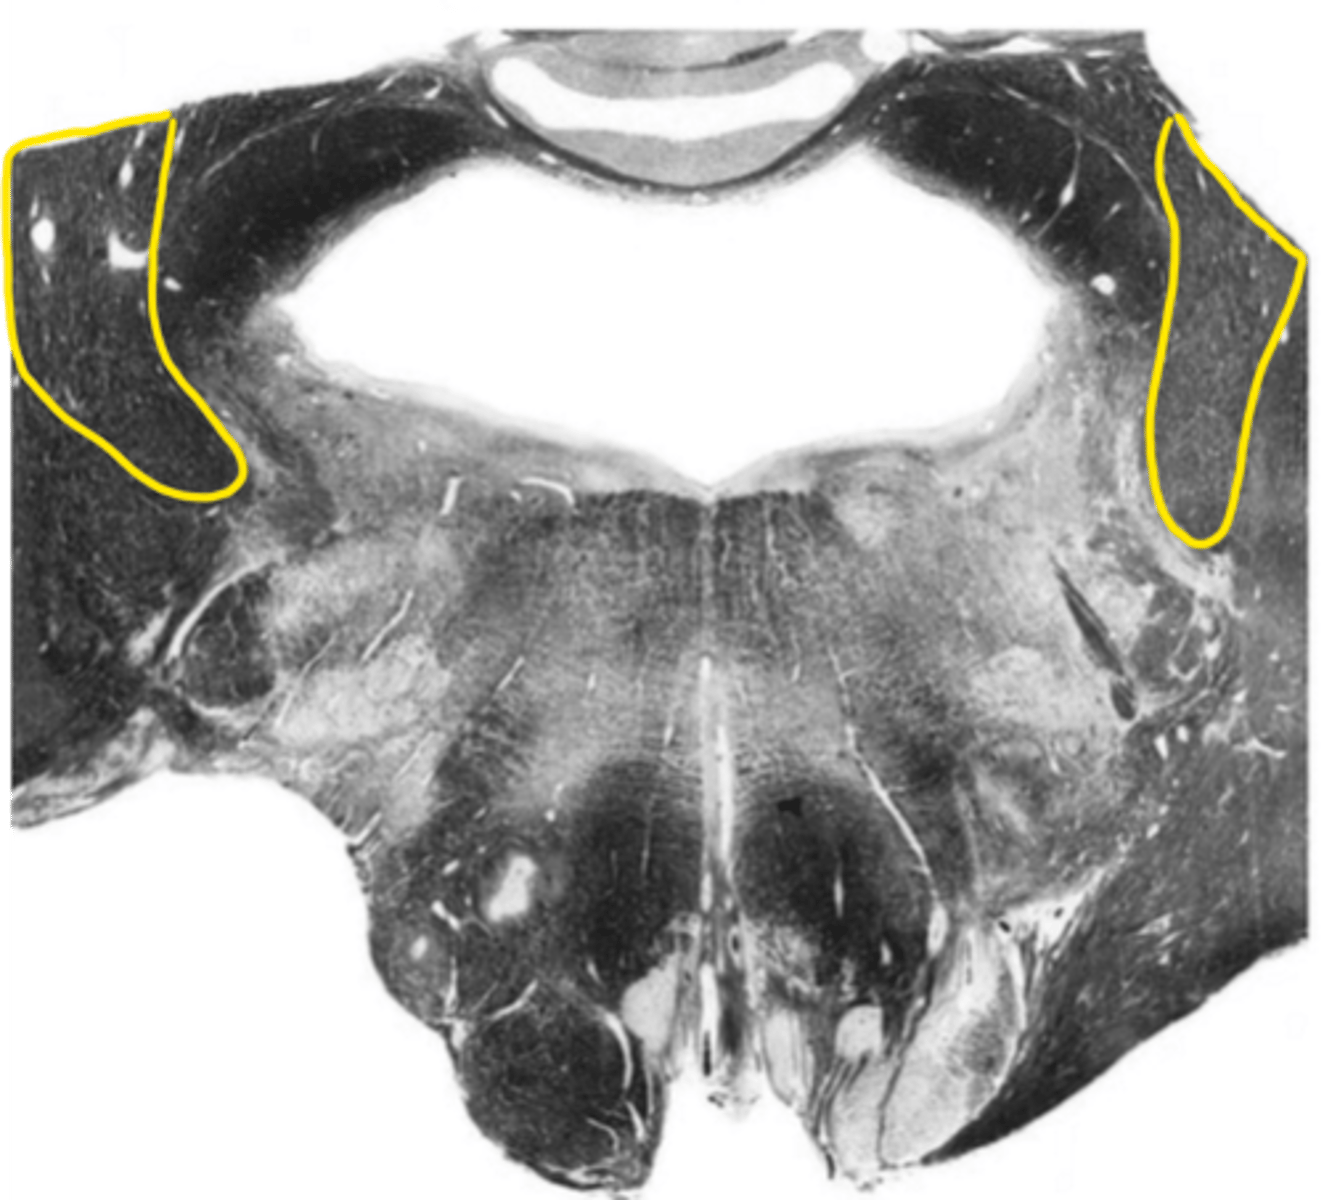

central canal

ID the space

central gray

ID the structure

hypoglossal nucleus

ID the nucleus

gracile nucleus

cuneate nucleus

inferior cerebellar peduncles

reticular formation

internal arcuate fibers

ID the fibers

principle olivary nucleus

medial lemniscus

corticospinal fibers

anterior median sulcus

posterior median sulcus